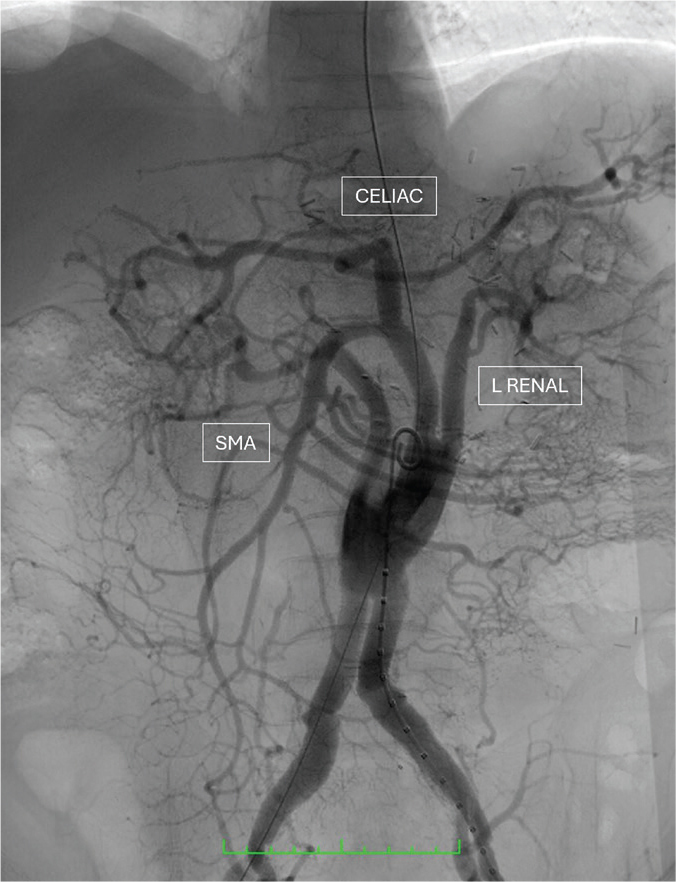

Repair of complex aortic aneurysms such as those involving the thoracoabdominal and pararenal aorta presents a formidable challenge for surgeons with significant perioperative morbidity and mortality. A hybrid procedure combining renovisceral debranching with endovascular aneurysm exclusion has been developed as an alternative approach for high-risk patients. This paper reports our initial experience with hybrid repair for these complex aortic diseases in three high-risk patients.